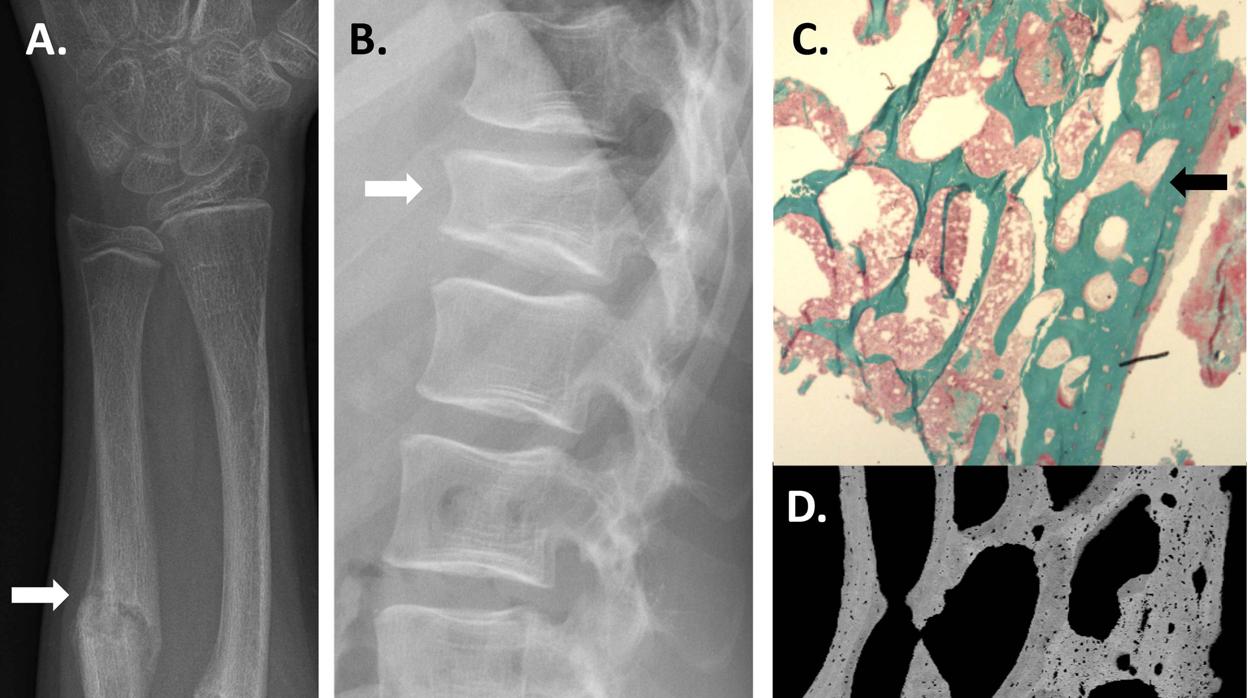

Pie de foto: La salud ósea de los participantes del estudio se evaluó mediante radiografías (A, B) y muestras de biopsia ósea (C, D). Los pacientes tuvieron en la infancia por ej. Fracturas recurrentes de antebrazo (A) y fracturas de compresión espinal (B). La evaluación histológica de las biopsias óseas mostró (C) que la estructura ósea (verde), especialmente en el hueso cortical, era anormalmente frágil y osteoporótica. Una evaluación más detallada de las biopsias óseas mostró que el grado de mineralización ósea se redujo y el tejido óseo era poroso (D), lo que redujo la resistencia ósea Outi Mäkitie Lab

El examen de las muestras de hueso recogidas de tres pacientes demostró que su tejido óseo difería del tejido óseo normal: el número de células óseas era atípica y la mineralización ósea estaba alterada. Los cambios fueron particularmente claros en el hueso cortical, la capa externa del hueso, la región con la expresión más abundante del gen SGMS2.